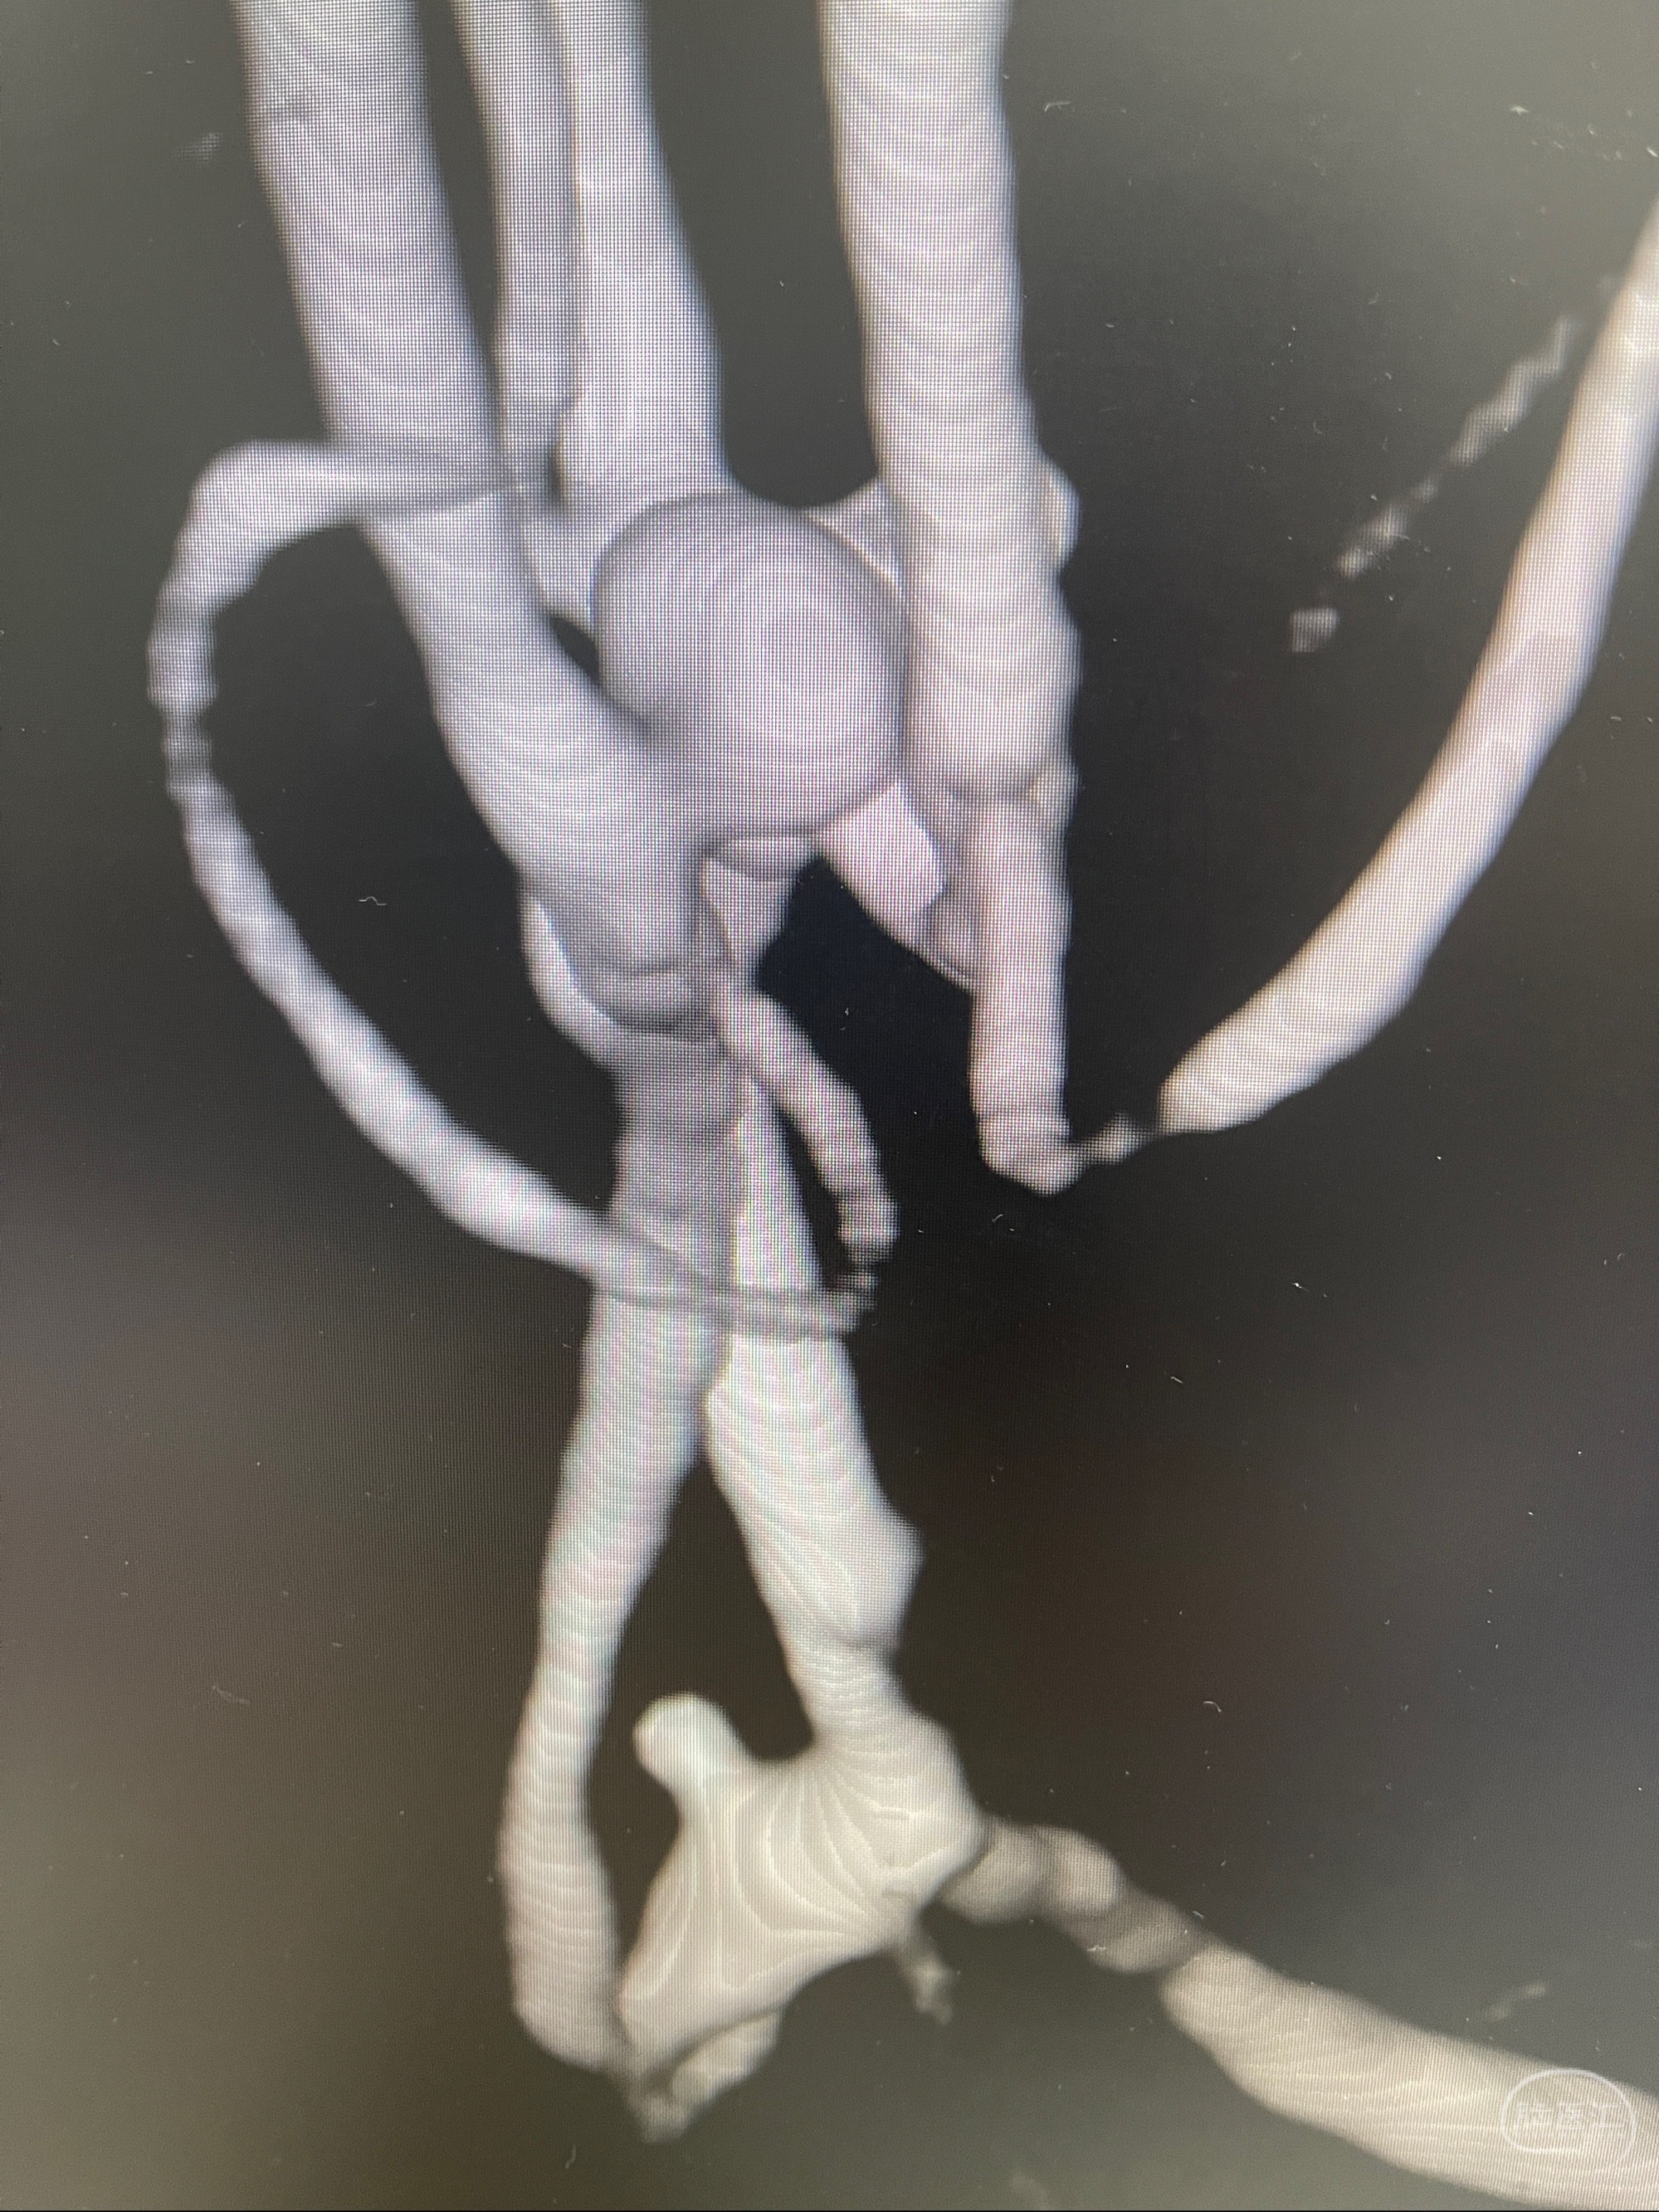

检查;2023-7-18 抚州市第一人民医院 头颈部CTA:左侧大脑前动脉A2段动脉瘤,左侧颈内动脉C4段轻度狭窄,右侧颈内动脉C6段中度狭窄

1.左侧大脑前动脉远侧段(A2-A5)动脉瘤

2023-08-23DSA:左侧前交通动脉瘤,左侧A3/4交界处多发动脉瘤